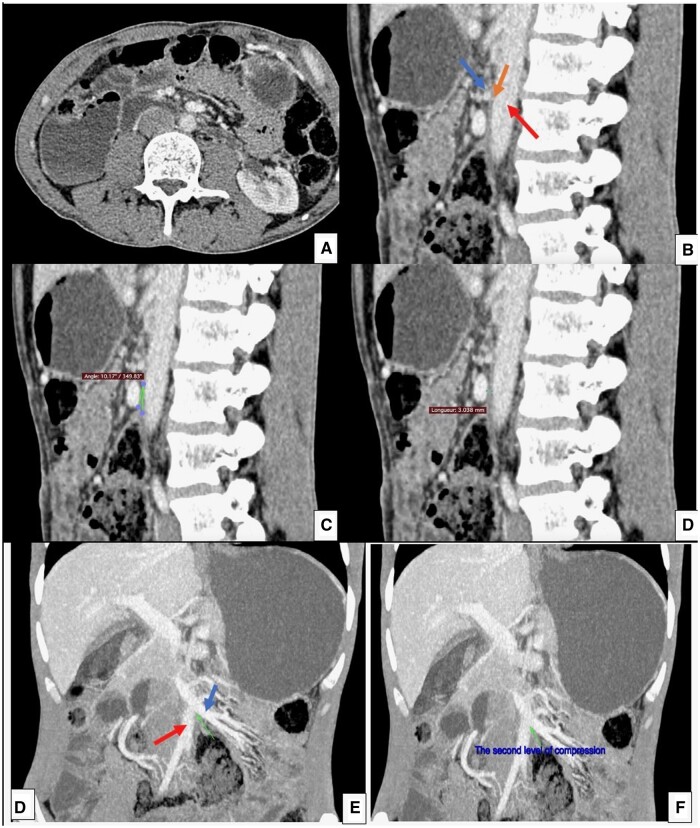

Superior mesentery artery (SMA)-like syndrome is an increasingly used term to describe vascular compression of the third duodenal portion between structures other than the superior mesenteric artery and aorta. Although rare, this clinical condition is as serious as true SMA syndrome and requires similar management. However, the diagnostic criteria are not well established yet and require a case-by-case analysis, including a review of various clinical symptoms, especially evolving ones, as well as radiological imaging and effectiveness of conservative therapeutic manoeuvres. The presented case involves a double vascular compression in a 50-year-old woman with no medical history, one of which is between 2 venous structures. The patient had been experiencing recurrent abdominal pain, vomiting, and distension for a long time. Laboratory tests were normal, and gastroesophageal endoscopy revealed Barrett's oesophagus. CT-enterography revealed 2 duodenal vascular compressions. Dietary measures were initiated with close follow-up. To the best of our knowledge, this is the first reported case in the world literature and adds to the existing body of SMA-like syndromes.